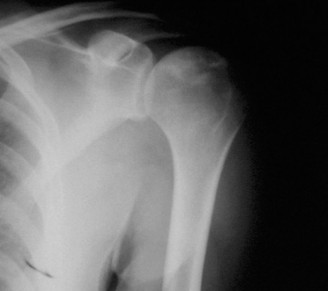

The correct answer is (E). Given that her rotator cuff has atrophied and has fatty infiltration to the point where there are equal parts fat and muscle, this is considered an irreparable rotator cuff tear. Repair should not be attempted because of poor outcomes following repair (see last two paragraphs of this discussion below). A reverse total shoulder arthroplasty is an alternative to repair that should be used in cases of massive, irreparable rotator cuff tears. It is a semi-constrained prosthesis that restores function in patients with massive rotator cuff tears by constraining a concave humeral cap inferior to a semispherical glenoid component (glenosphere). This creates an inferior force-couple and a fulcrum that replaces the stabilizing function of the infraspinatus maintaining a center of rotation around which the shoulder can move. This allows the deltoid to abduct and flex the shoulder without causing the humerus to migrate superiorly and about the acromion. In an elderly patient with a massive, irreparable rotator cuff tear (as in this patient), a reverse total shoulder arthroplasty is the procedure of choice.

It should be noted that reverse total shoulder arthroplasty is also the procedure of choice in patients with cuff-tear arthropathy (aka rotator cuff arthropathy). Characteristics of cuff-tear arthropathy include superior migration of the humerus due to a massive rotator cuff tear, glenohumeral joint destruction, subchondral osteoporosis, and humeral head collapse (see Fig. 2–17). A reverse total shoulder

arthroplasty in this case serves the purpose of eliminating pain caused by glenohumeral joint arthritis while restoring functional motion and is the procedure of choice in patients with cuff-tear arthropathy.

Figure 2–17_X-rays of a patient showing evidence of cuff tear arthropathy. The humerus is migrated superiorly, the glenohumeral joint is destroyed, there is subchondral osteoporosis, and the humeral head is collapsed. (From Ecklund KJ, Lee TQ, Tibone J, Gupta R. Rotator cuff tear arthropathy. _J Am Acad Orthop Surg. 2007;15(6):340–349.)